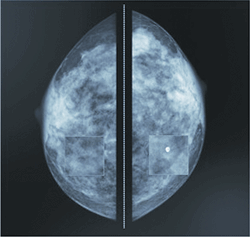

Med Mammo is a mammography diagnostic workstation which combines ease of use and high performance features

With Medecom’s Med Mammo breast imaging workstation, one can include reading of tomosynthesis images and other multi-modality radiology examinations in the regular mammography reading workflow. This significantly increases efficiency as the need to move to a dedicated modality workstation is eliminated.

Mammography studies from multiple vendors are automatically scaled and aligned to ensure optimal side by side comparison. Medecom has improved this critical element of digital mammography reading, to make it possible to view and report on all forms of breast imaging (MRI, ultrasound, digital breast tomosynthesis and X-ray) from any vendor on a single client interface.